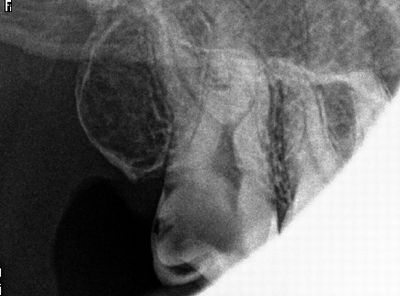

左上6番、セメントが詰めてある。冷水痛(+)、自発痛(+-)、打診痛(+)

うーん、こりゃダメなんじゃ・・・

セメント除去したら、ドワァと出血。こ、こりゃ直接覆髄じゃダメ多分。

レーザー当てたりヘモデントで止血を試みたがダメでしたので、

生活歯髄切断法に切り替えました。